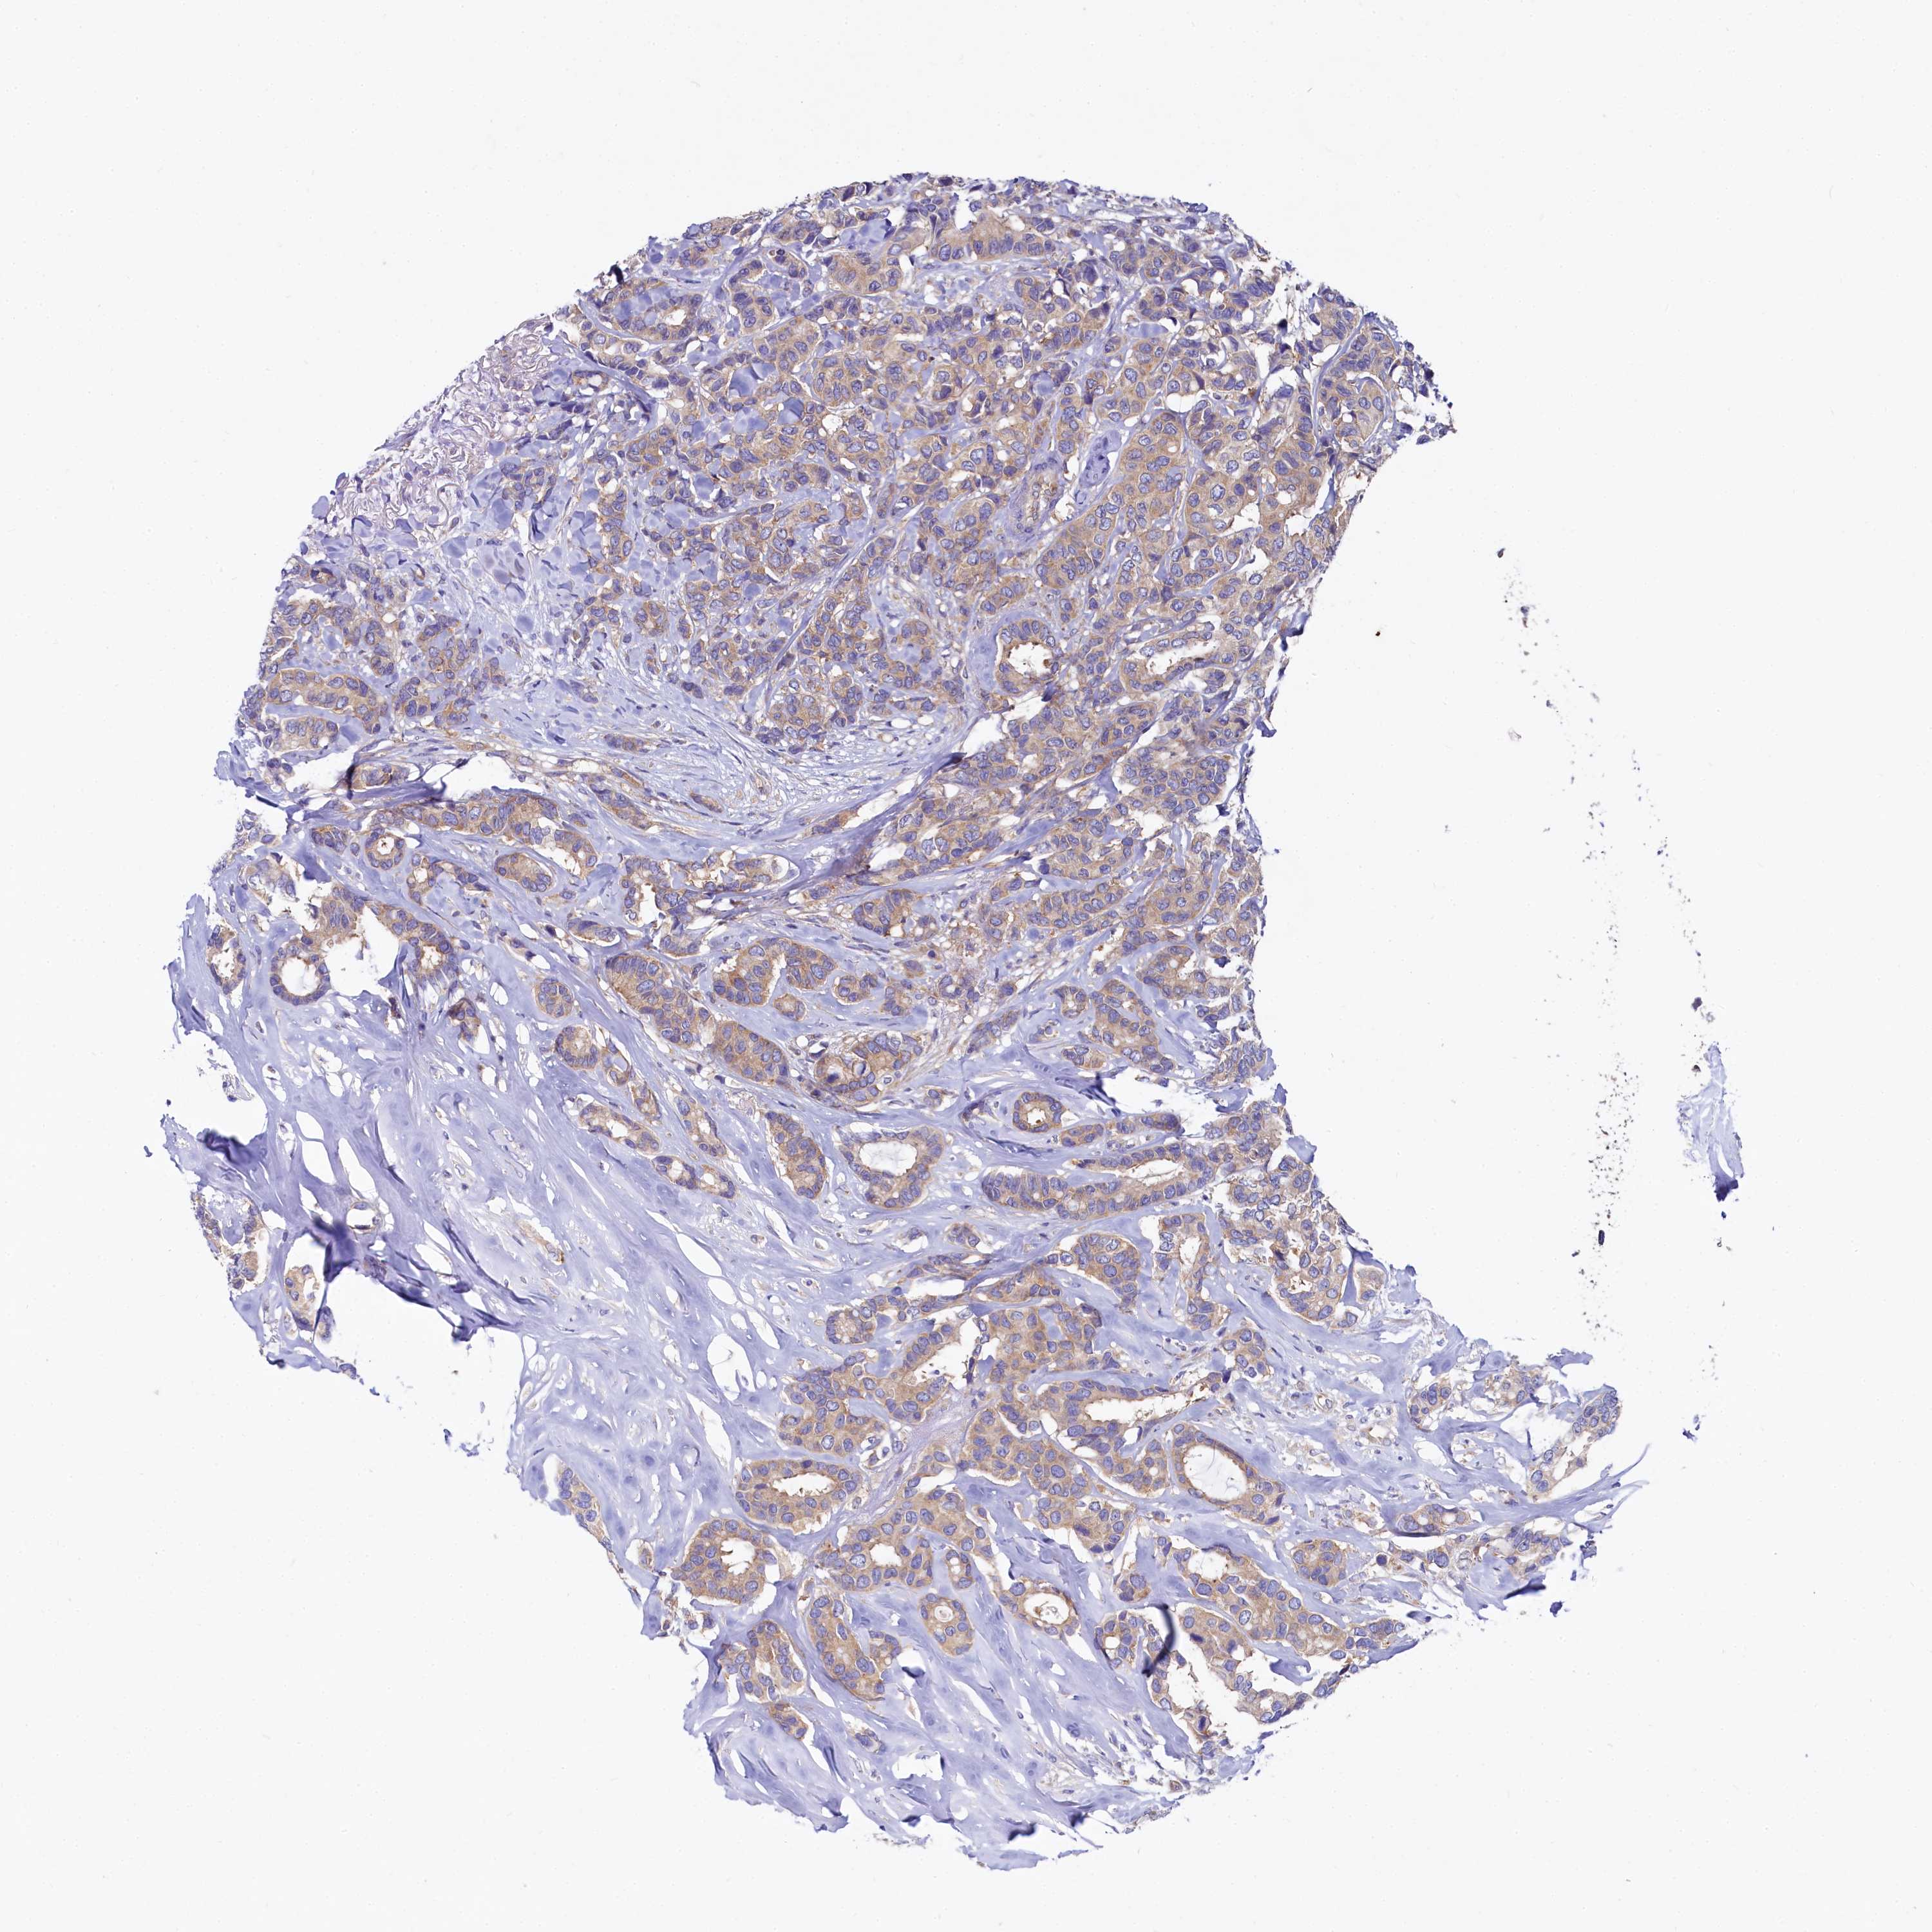

CANCER BREAST CANCER Show tissue menu

BRCA TCGA BRCA VALIDATION PROTEIN EXPRESSION